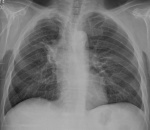

Эмпиема?

Поддерживаю. Пневмогидроторакс осумкованный, возможно, ятрогенного генеза. Возможно эмпиема. Так же не исключаются изменения в компремированной легочной ткани.

Нарушу ваше единодушие). Полисегментарная пневмония слева, осложненная деструкцией и осумкованным паракостальным и междолевым гидротораксом.

Тогда, мне кажется, двусторонняя полисегментарная. Без КТ достоверно сказать не могу, что в легочной ткани инфильтрация, все-таки имеется сжатие левого легкого массивным мешком эмпиемы, плюс на фоне выраженной плевральной реакции достоверно оценить снижение пневмотизации, на мой взгляд, невозможно. Справа же на фоне деформированного и обогащенного легочного рисунка тоже мерещатся (поскольку и оно поддавлено смещенным средостением) фокусы инфильтративного характера. Достоверно могу заключить только осумкованный пневмогидроторакс, а сомнения же выразить только в описании и рекомеендовать КТ. И в плане мезотелиомы настороженность бы написать.

Эмпиема. С уверенностью сказать не могу, но ставлю на абсцесс в S6 слева.

"Уровень" появился после пункции.

Выскажусь за центральный рак.Клапанный ателектаз.

Центральный C-r+ателектаз справа.